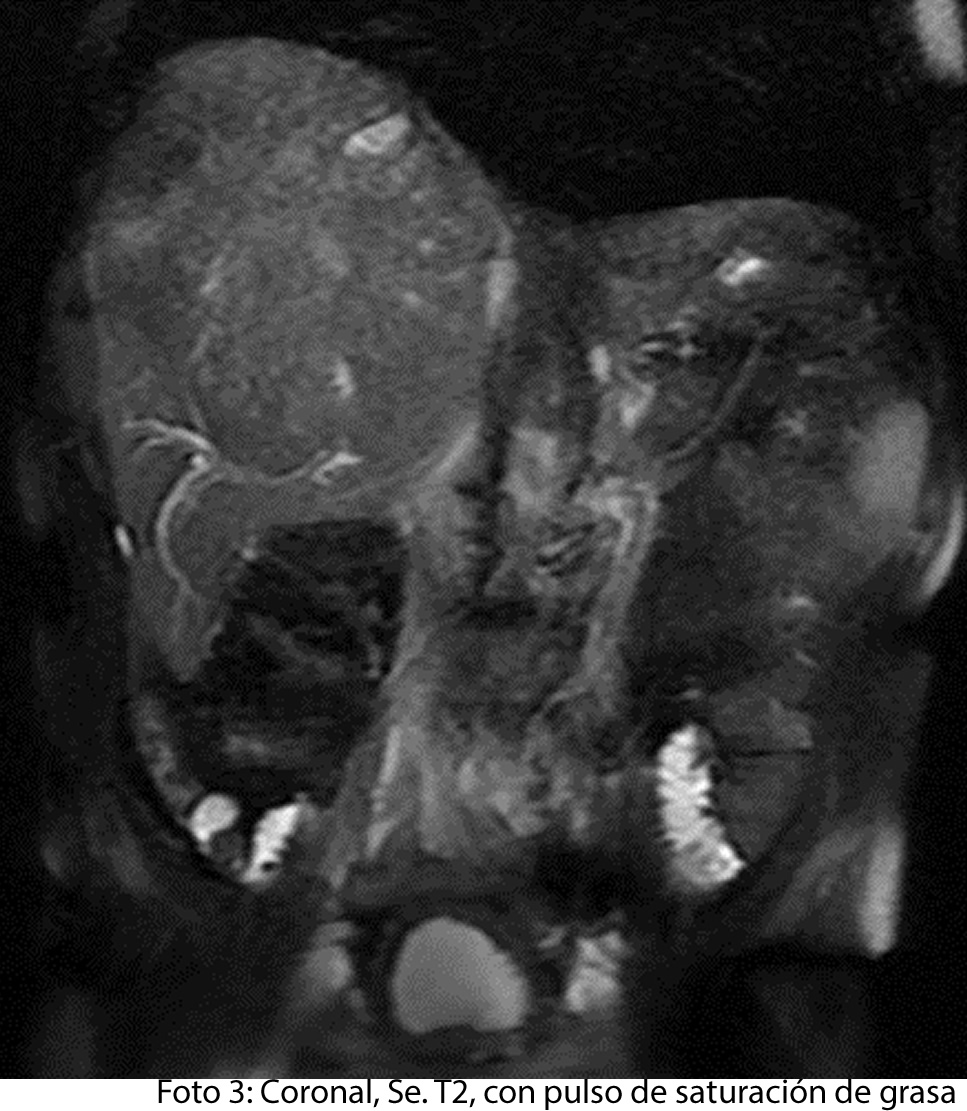

HALLAZGOS IMAGENOLOGICOS

• HEPATOCARCINOMA FIBROLAMINAL QUE COMPROMETE TODO EL LÓBULO DERECHO DEL HÍGADO

Fase arterial demuestra vasos aferentes dependientes de la arteria hepática que causa realce temprano de la masa en estudio. Compresión extrínseca de vena porta y vena cava inferior.

Es un método utilizado en el cual podemos observar una gran masa localizada en los segmentos del hígado también se puede medir el diámetro de la masa, el hepatocarcinoma también puede presentar focos hemorrágicos y además podemos captar de manera heterogénea el medio de contraste intravenoso. En los hepatocarcinomas podemos ver obstruyendo parcialmente la vena porta. Adenomegalias los cuales nos indican Los hallazgos como primera posibilidad diagnóstica, carcinoma hepatocelular fibrolamelar (CHC-FL).